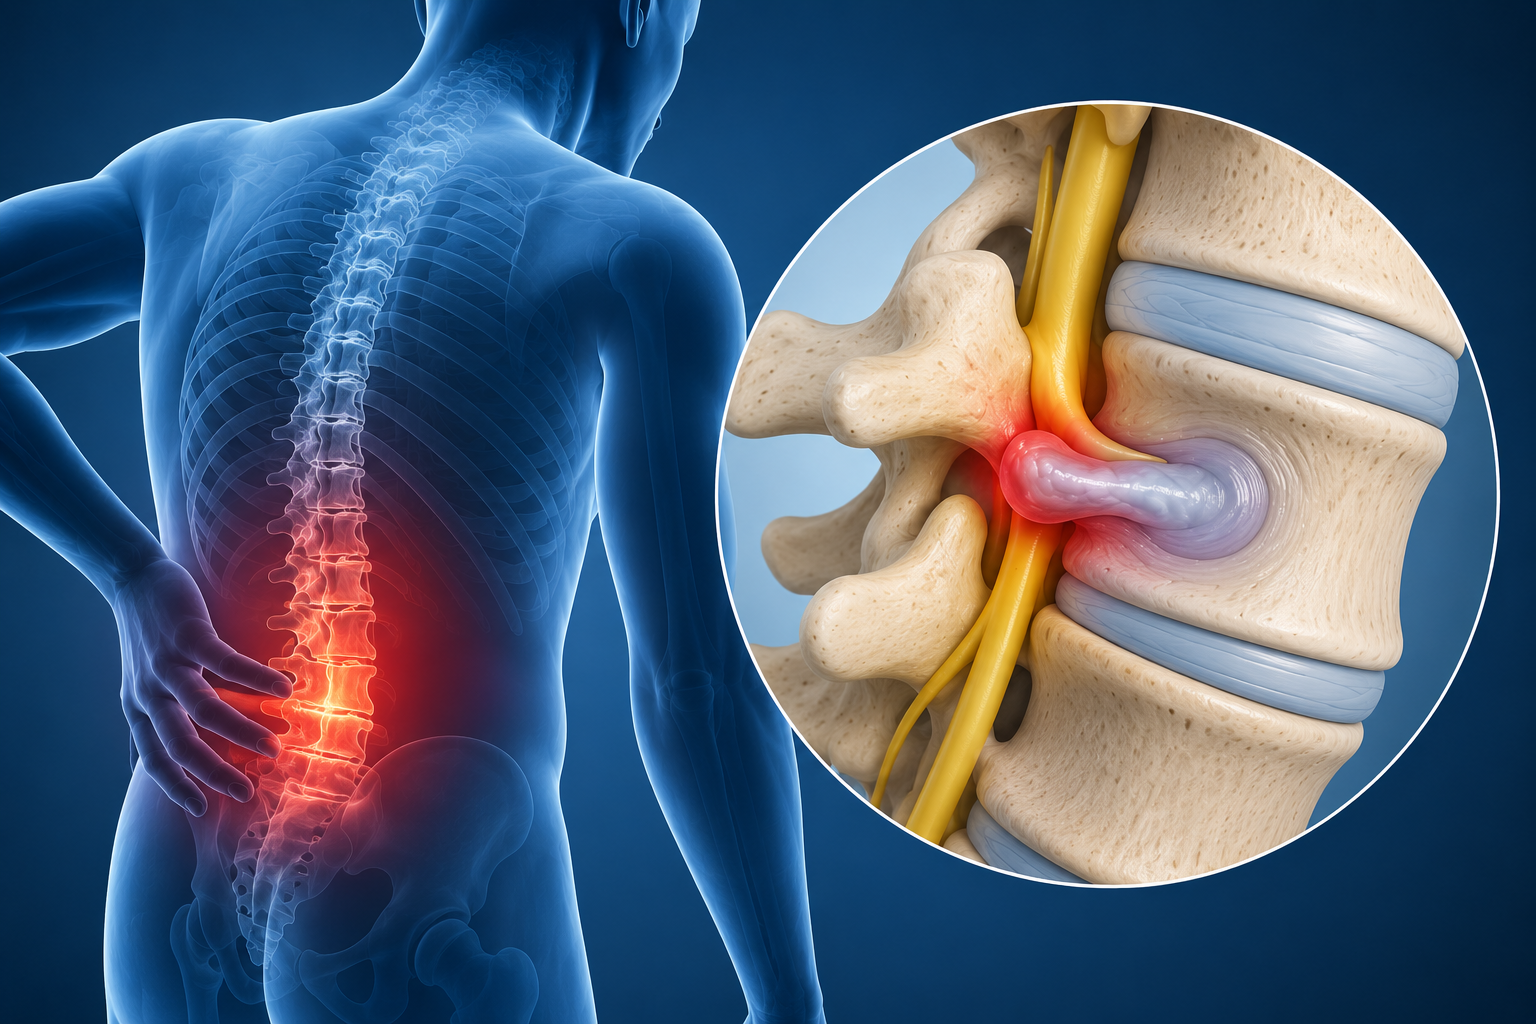

Hernia de Disco: Qué es y Cómo Afecta Tu Salud

## ¿Qué es una hernia de disco?La columna vertebral está formada por vértebras apiladas, separ...

Enfermedad del Disco Intervertebral: Causas, Síntomas y Soluciones

La enfermedad del disco intervertebral es una condición frecuente que afecta la columna vertebral, ...